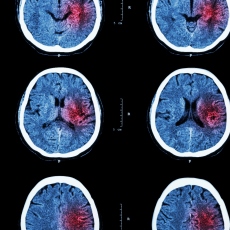

A stroke is a medical emergency. There are two types - ischemic and hemorrhagic. Ischemic stroke is the more common type. It is usually caused by a blood clot that blocks or plugs a blood vessel in the brain. This keeps blood from flowing to the brain. Within minutes, brain cells begin to die. Another cause is stenosis, or narrowing of the artery. This can happen because of atherosclerosis, a disease in which plaque builds up inside your arteries. Transient ischemic attacks (TIAs) occur when the blood supply to the brain is interrupted briefly. Having a TIA can mean you are at risk for having a more serious stroke.

Symptoms of stroke are:

- Sudden numbness or weakness of the face, arm or leg (especially on one side of the body)

- Sudden confusion, trouble speaking or understanding speech

- Sudden trouble seeing in one or both eyes

- Sudden trouble walking, dizziness, loss of balance or coordination

- Sudden severe headache with no known cause

It is important to treat strokes as quickly as possible. Blood thinners may be used to stop a stroke while it is happening by quickly dissolving the blood clot. Post-stroke rehabilitation can help people overcome disabilities caused by stroke damage.